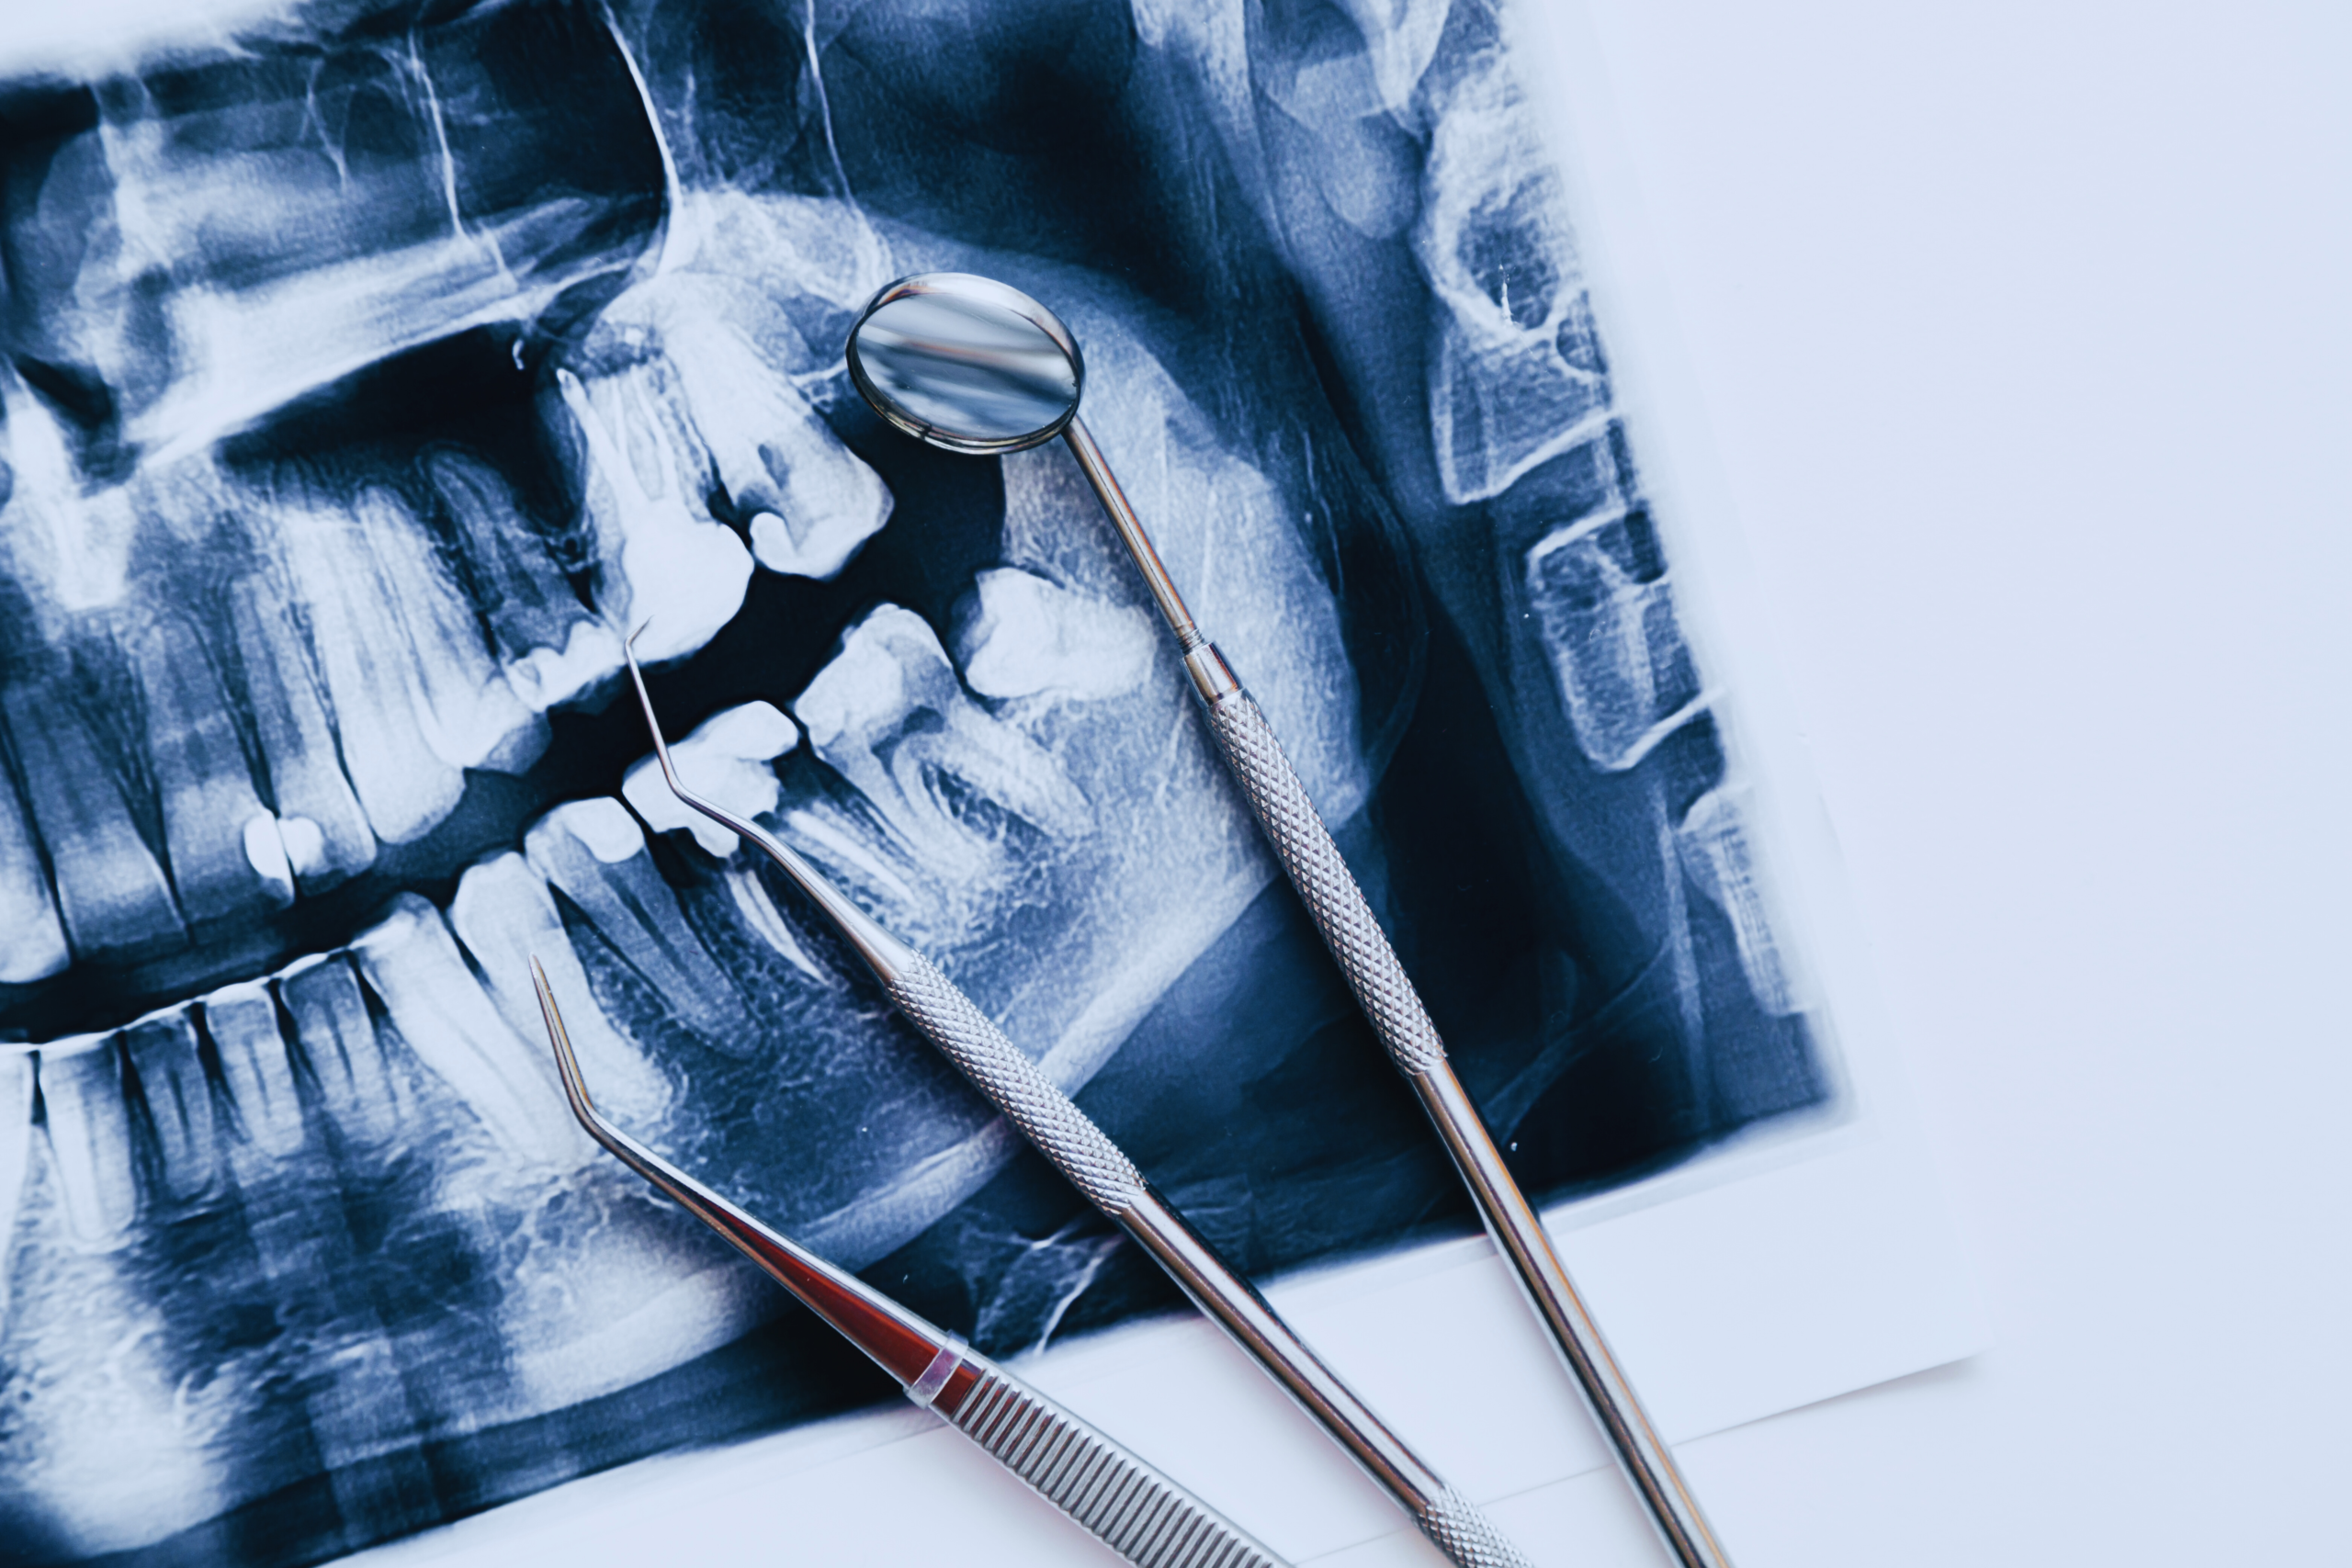

Dental x rays help us see what a visual exam cannot. At Diamond Dental Arts, we use modern dental imaging to evaluate teeth, roots, bone, and areas between teeth that are not visible during a regular exam. This helps us find concerns early and plan care with accuracy.

A dental x ray is an image of your teeth and surrounding structures captured with a very small amount of radiation. The goal is to create a clear picture on the computer so we can evaluate areas we cannot see with the naked eye. Dental imaging helps reveal changes inside a tooth, around the roots, and in the supporting bone.

Digital dental x rays at Diamond Dental Arts